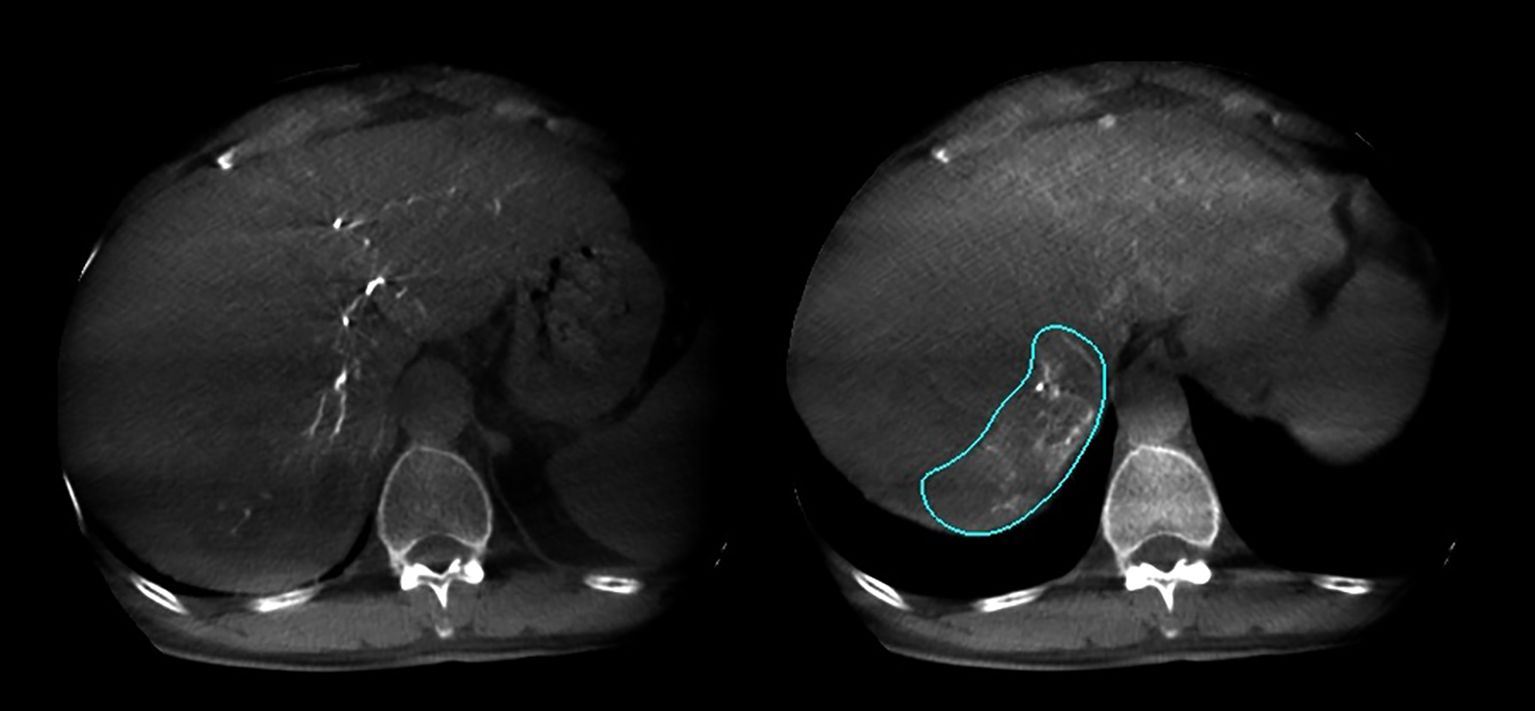

Figure 2

CT scan showing two axial images of the liver. The left image shows a normal liver appearance. The right image highlights a section with an irregular outline, possibly indicating a lesion or anomaly.

Figure 2. Arterial phase and delayed phase contrast-enhanced dual CBCT images acquired after injection into the tumor-feeding artery. The tumor area can be assessed based on the delayed phase image on the right.

In this study, 27 patients underwent liver DSA and dual CBCT scans prior to SIRT treatment to evaluate intrahepatic lesions, identify tumor-feeding vessels, ensure tumor enhancement, and exclude blood supply from collateral vessels. The Philips UNIQ FD20C (Philips Healthcare, Netherlands) was used. The dual CBCT was automatically triggered for image acquisition during the arterial and delayed phases. The flat panel detector rotated from -120° to +120°, enabling a comprehensive liver parenchyma scan. X-ray projections were acquired at 60 frames per second over 240°. The X-ray exposure was set to 120 kV, with a detector size of 48 cm and a pixel size of 4x4. Dual CBCT was performed during proper hepatic artery angiography by injecting 18 mL of contrast medium (Visipaque 320 mg I/ml) at a rate of 1.5 mL/s to evaluate total liver volume, right and left lobe volumes, and overall tumor burden. The first scan was initiated 4 seconds after the start of contrast injection, followed by a second scan commencing 8 seconds after the completion of the first, with each scan lasting 8 seconds. Subsequently, superselective DSA was conducted to assess the perfusion volume of specific hepatic arterial branches and the corresponding tumor volumes. For these injections, the contrast infusion rate was typically set at one-tenth of that used for conventional angiography. The total injection duration was defined as the time required for parenchymal opacification plus the rotation time of the imaging system, thereby ensuring that image acquisition occurred when the tumor region and its feeding arteries reached peak contrast enhancement. The total contrast volume administered was calculated as the product of the selected injection rate and injection duration. Contrast-enhanced dual CBCT data allowed precise measurement of the target liver lobe volume and tumor burden via a 3D segmentation tool. Arterial and delayed phase CBCT images enabled tumor area assessment, particularly during the delayed phase image (Figure 2). Injection into the segmental right hepatic artery provided detailed tumor perfusion area assessment. Both arterial and delayed phase images, especially the delayed phase (Figure 3), offered precise information on tumor perfusion.